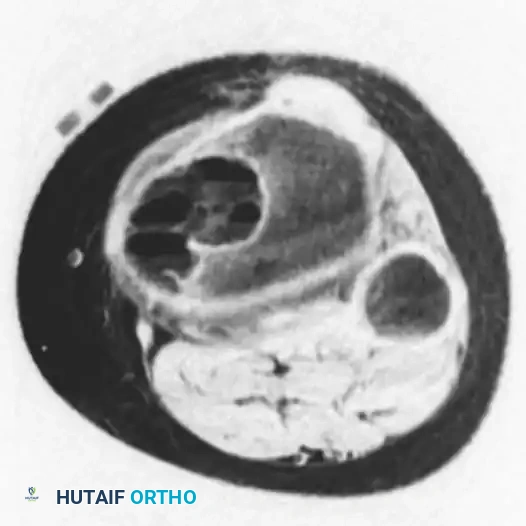

Advanced Imaging (MRI and CT):

MRI is the gold standard for differentiating an ABC from a UBC or a necrotic malignancy. The hallmark MRI finding of an ABC is the presence of multiple double-density fluid-fluid levels within intralesional septations. These levels represent the settling of blood degradation products (serum layered over red blood cells) within the cavernous spaces.

Coronal MRI image demonstrating the multiloculated nature of the lesion.

Axial MRI image clearly showing multiple fluid-fluid levels, highly consistent with an aneurysmal bone cyst.